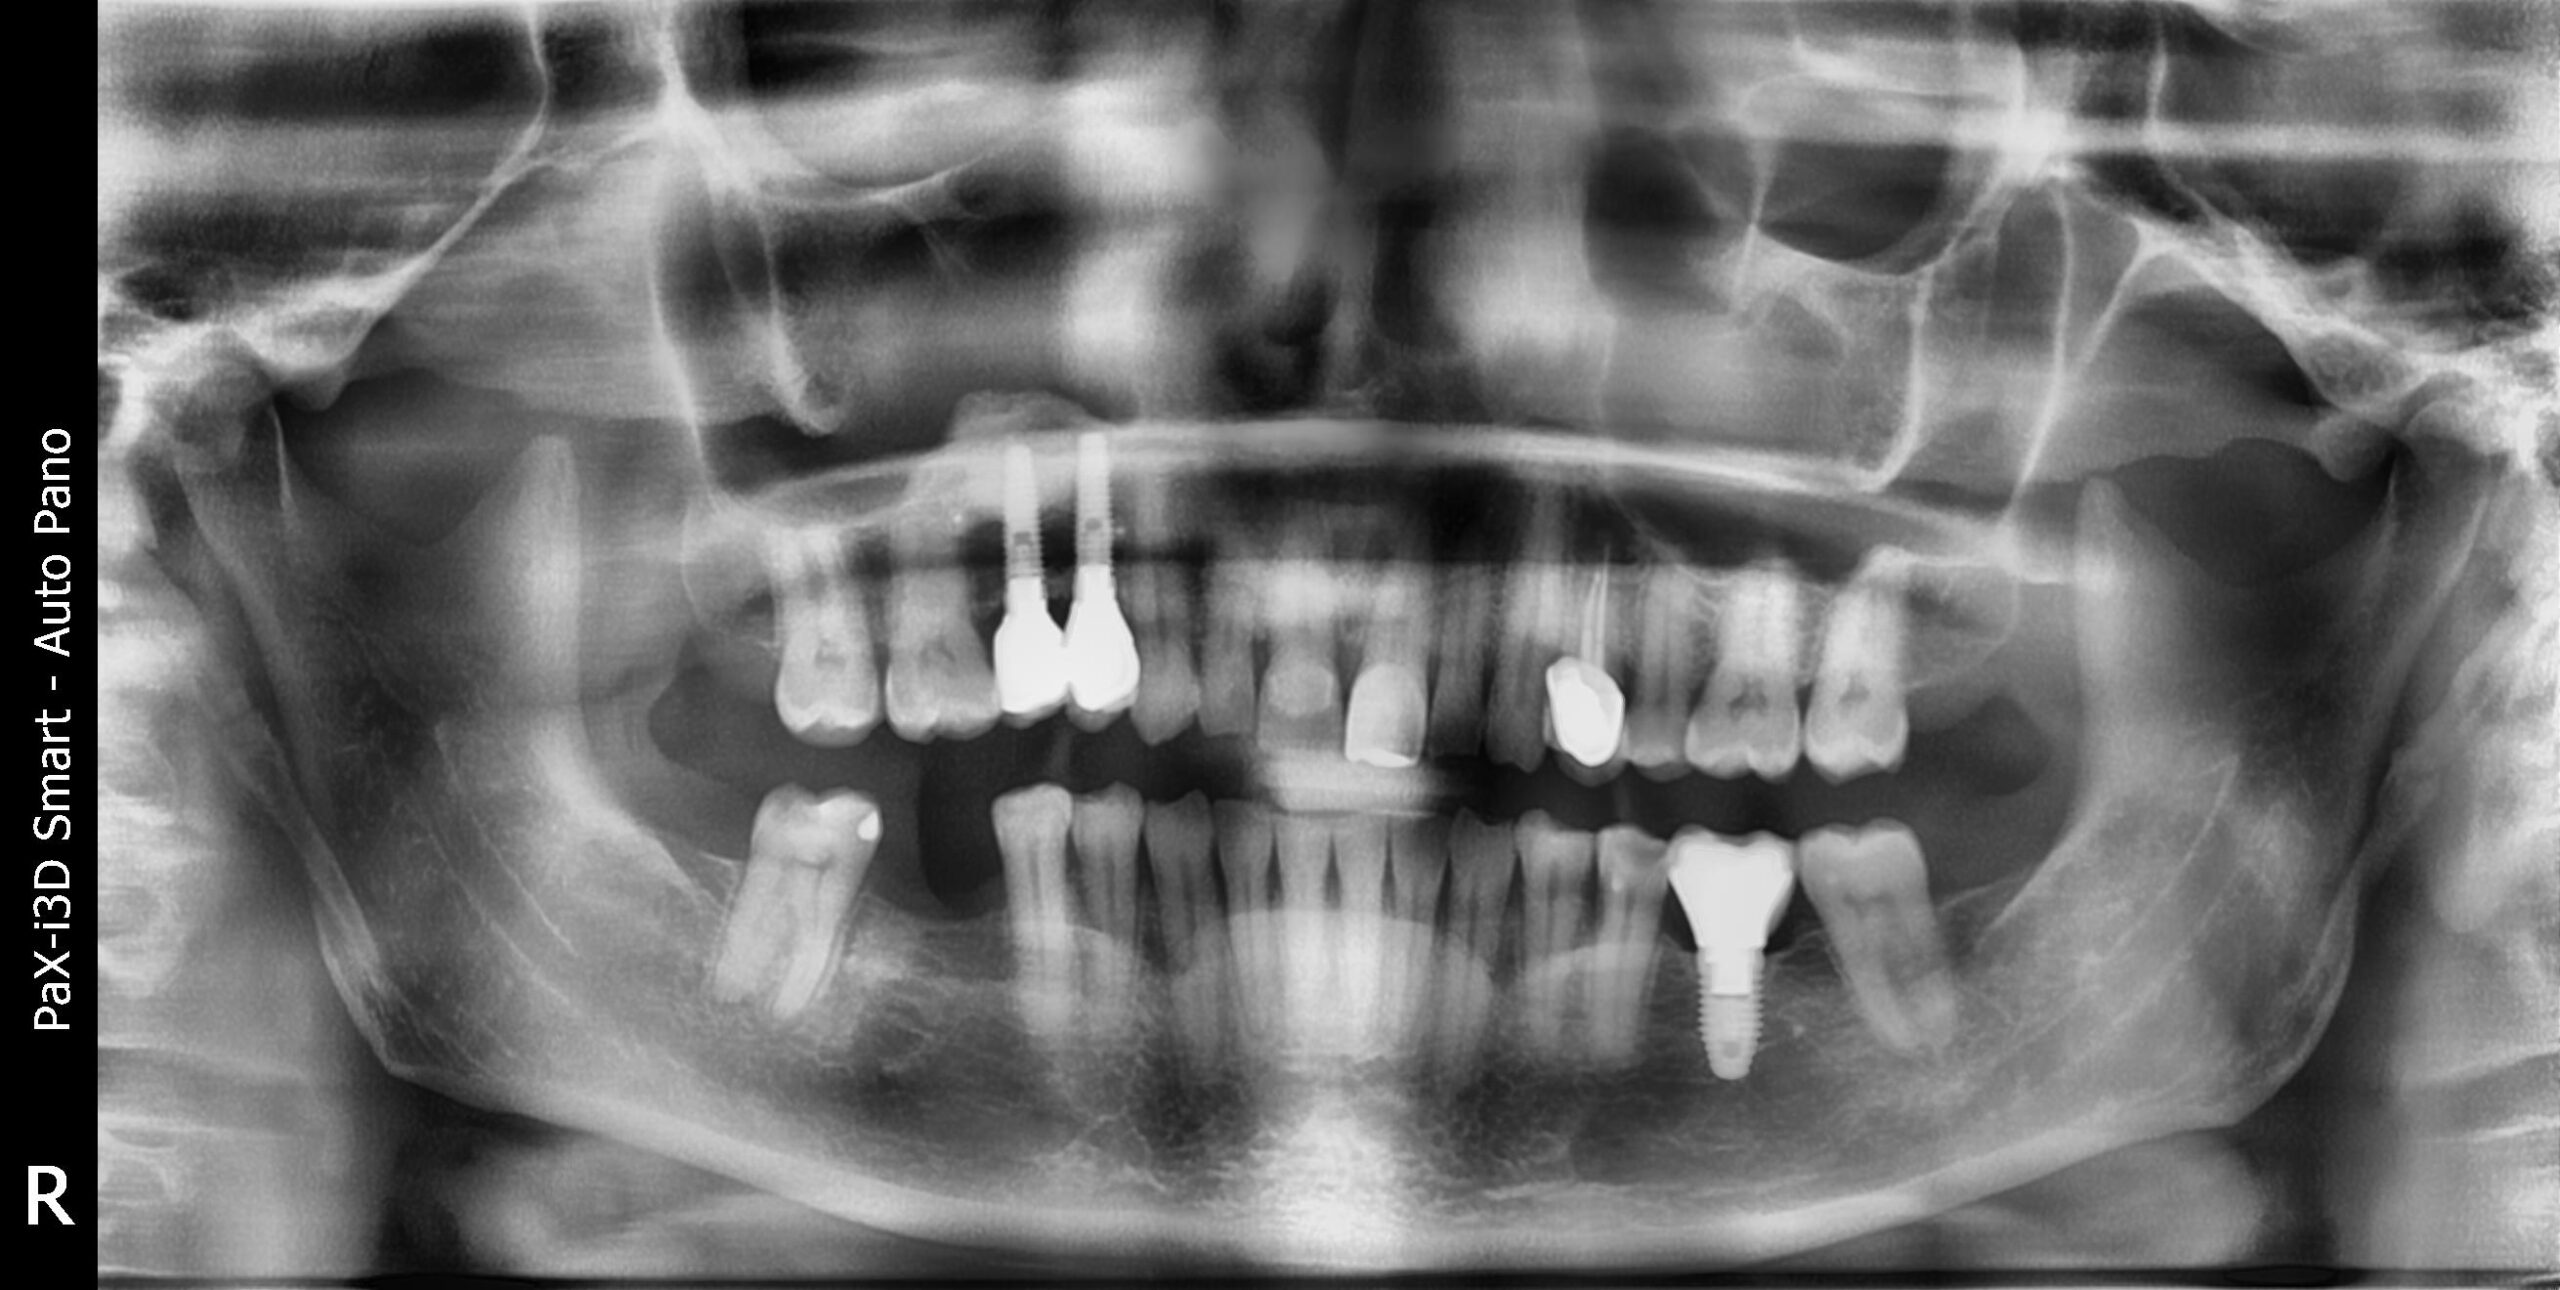

4. Ausencia de varias piezas

Colocación de implantes dentales